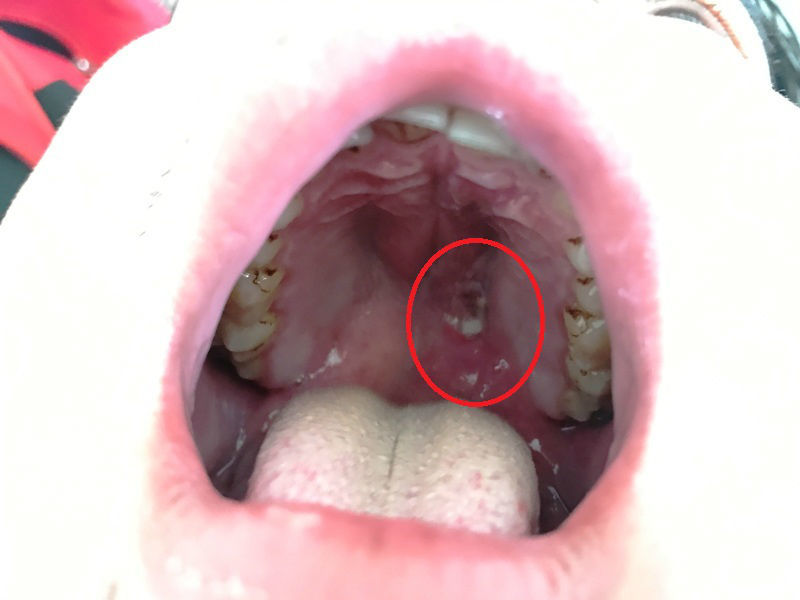

| Vị trí viên đạn bi trong vòm họng nam bệnh nhân |

Trong lúc đang thổi, anh Phong vô tình dùng tay bóp vào bộ phận cò khiến viên đạn bay ra, găm thẳng vào vòm họng, miệng đầy máu.

Thấy tình trạng người bệnh nặng, anh Phong tiếp tục được chuyển vào Bệnh viện Chợ Rẫy. Mới đây, sau 2 giờ phẫu thuật, khoa Tai mũi họng đã gắp viên đạn bi ra ngoài.